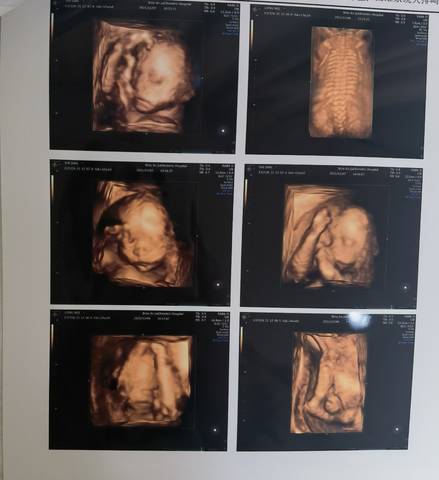

请帮忙看一下右下角最后一张图是哪个部位

亲爱的,这个部位是看不太出来的呀,正常情况下只要孩子发育好的话,都是没有什么关系的呢。

你好。我们是判断不了男宝宝跟女宝宝的,孕期定期检查,我觉得宝宝健康就好的。祝心想事成 。